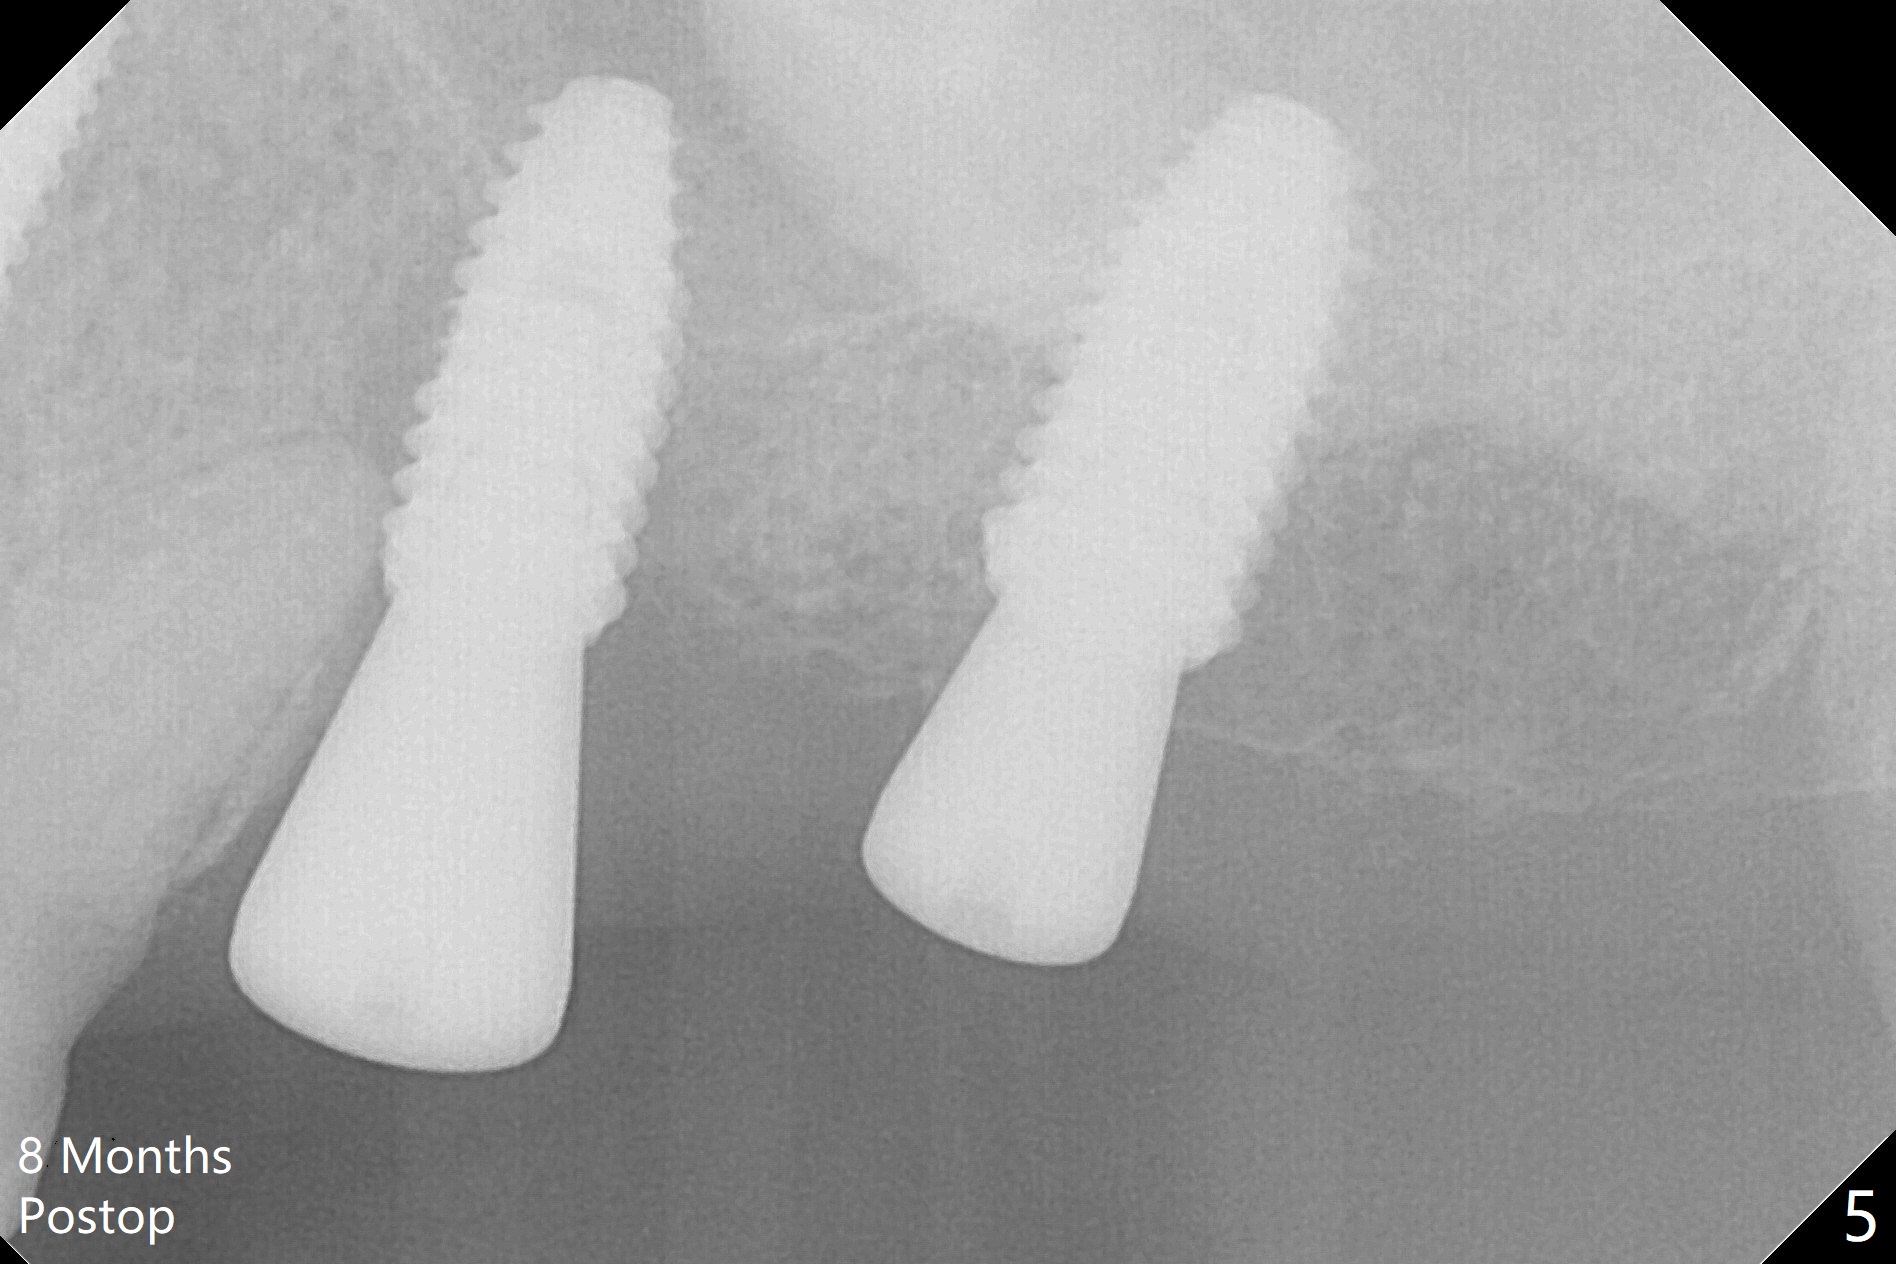

Immediately postop PA (Fig.1) and panoramic X-ray (Fig.2) show that the implant at #14 is close to the root of the tooth #13.  Clinic exam and CBCT (Fig.3,4) demonstrate a reasonable separation.  The trajectory of #14 osteotomy may be altered while using 2.8 mm round drill for 7-9 mm for sinus lift (free hand).  There is no bone loss 8 months postop (Fig.5).

#15 looks good as planned and #14 seems quite close to the neighboring tooth and quite off from the planed position.